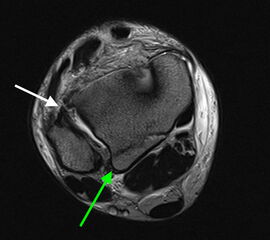

Die Magnetresonanztomographie stellt aktuell den Goldstandard in der Diagnostik von Syndesmosenverletzungen dar (Szeimies 2013). Beschrieben sind eine Sensitivität von 100% und eine Spezifität von 93% bei Verletzungen des AITFL, sowie eine Sensitivität und Spezifität von 100% bei Verletzungen des PITFL. Darüber hinaus ermöglicht das MRT weitere ligamentäre, chondrale oder intraossäre Verletzungen zu detektieren. Bei chronischen Syndesmosenverletzungen sollte eine MRT-Diagnostik mit Kontrastmittel (KM) intravenös durchgeführt werden, da diese eine höhere Spezifität und Sensitivität im Vergleich zur nativen MRT-Bildgebung aufweist. Durch die zusätzliche Gabe von KM können durch eine Mehranreicherung des KM im Bereich der Syndesmose Rückschlüsse auf das Vorhandensein einer chronische Instabilität gezogen werden 41.